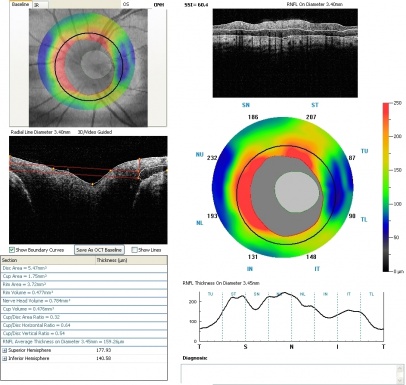

The optic nerve appears large and funneled.[4] There is a conical excavation of the dysplastic optic disc and the surrounding posterior pole, filled with glial tissue.[3] An increased number of straight retinal vessels arise from the disc margin and peripapillary pigmentation can also been seen.[3] The term “macular capture” is used when the macula is involved in the excavation.[4] Contractions of the optic nerve have also been described and is attributed to the presence of myofibroblasts in the papillae.[3] Due to unilateral involvement in most cases, an afferent pupillary defect can be noted.[3]

There is no treatment for morning glory disc anomaly. However it is important to optimize visual acuity to prevent amblyopia.[3] Dilated fundus exams should be done to detect serous retinal detachments that tend to originate in the peripapillary area and extends to the posterior pole.[4] These examinations are particularly important given that serous maculopathy is a recognized complication associated with Morning Glory Anomaly.

- ↑ 2.0 2.1 Cennamo, G et al. 2009. Evaluation of Morning Glory Syndrome with Spectral Optical Coherence Tomography and Echography. Ophthalmology. 117:6, p1269–1273